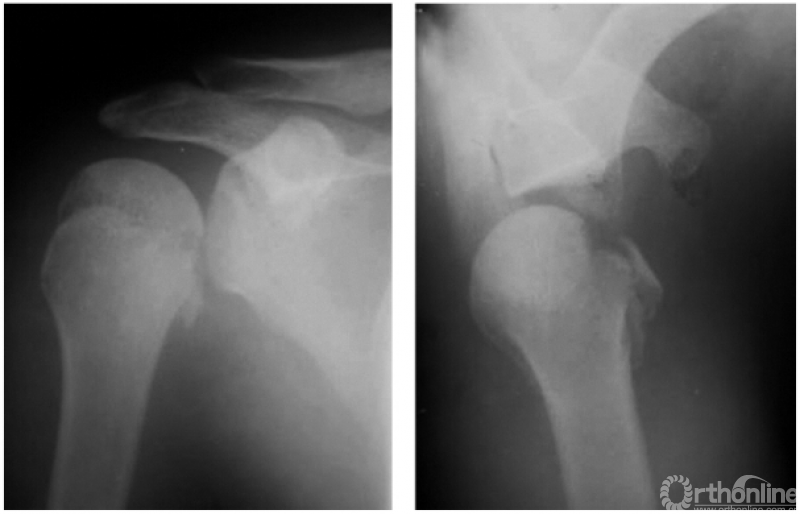

例1:肩关节盂下脱位(如下图)。

例2:希-萨(Hill-Sachs)二氏损伤。肱骨头后外侧劈裂骨折形成楔形缺损,骨折块下移并肩关节喙突下脱位(如下图)。